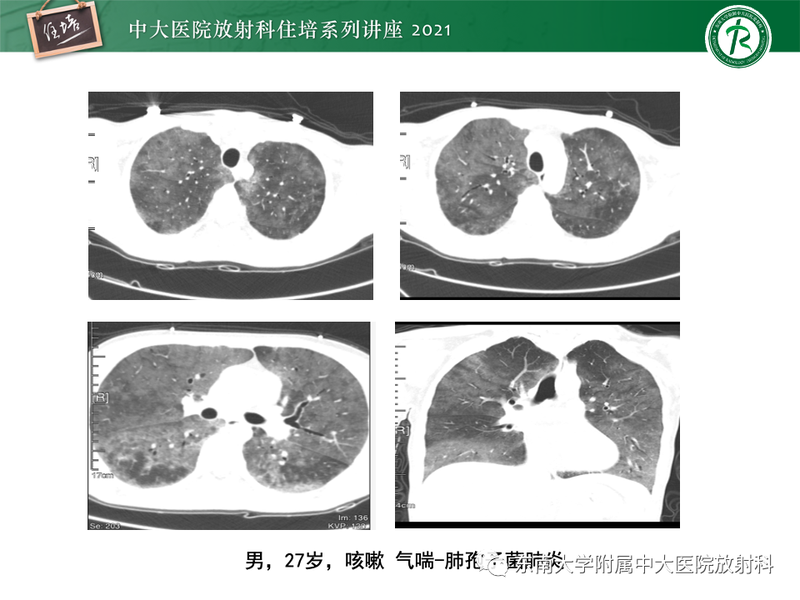

常见细菌性肺炎、病毒性肺炎影像诊断与鉴别